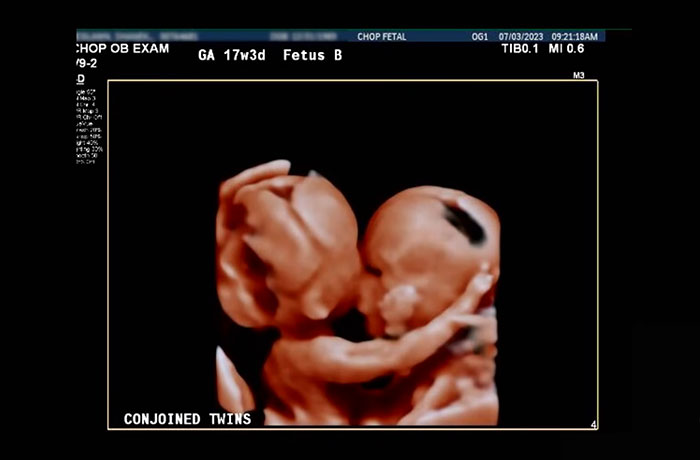

Share icon Image credits: Children’s Hospital of Philadelphia Share icon Image credits: Children’s Hospital of Philadelphia The twins reportedly shared the lowest part of their sternum, diaphragm, abdominal wall, and liver. The hospital explained in an official statement: “This set in motion the plan for preparing the boys’ first milestone: a safe birth.” On September 29, 2023, the boys were born, collectively weighing about 6 lbs (approximately 2.7 kg). After 10 months of planning, the eight-hour operation to separate Amari and Javar took place on August 21, People reported. Once separated, the boys’ abdomens were closed and rebuilt, using layers of mesh and plastic surgery techniques to stabilize each one.

Celebrating their first birthday on September 29, twins Amari and Javar Ruffin were successfully separated the previous month